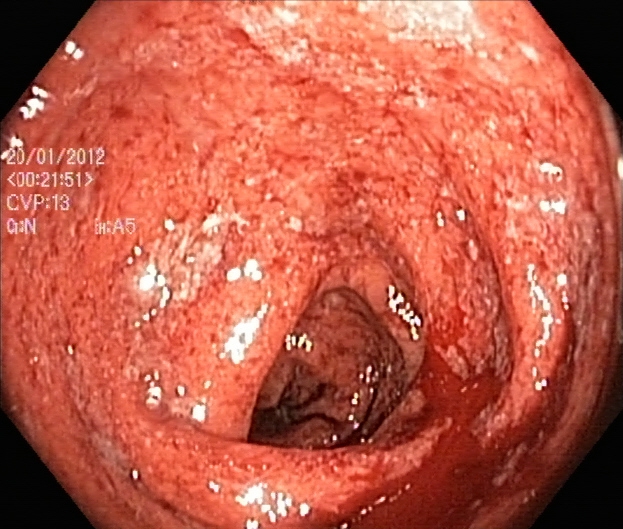

An automatic and efficient Computer-Aided Diagnosis (CAD) system in a clinic could assist medical experts during the endoscopic and colonoscopy procedure to improve the detection rate by finding unrecognized lesions and act as a second observer by providing better insights to the gastroenterologist concerning the presence and types of lesions. With this inspiration, we conducted five experiments to classify 161616 classes of GI tract conditions for the Medico Multimedia Task at MediaEval 2018 (Pogorelov et al., 2018b). One example for each of the 16 classes is depicted in Figure 1.

Figure 1. Sample images of GI findings. Each image represents one of the 16 classes from the dataset used for the Medico 2018 challenge (Pogorelov et al., 2017c, a).